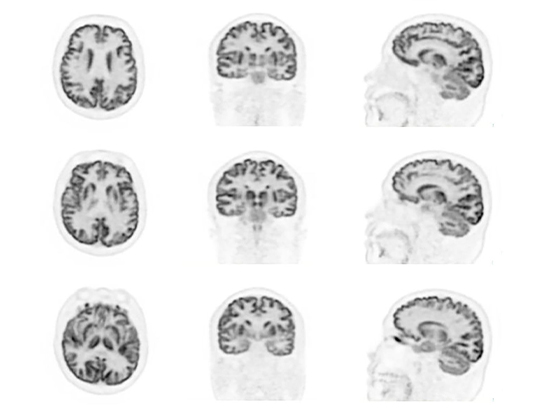

The data-driven head motion correction algorithm detects motion from list-mode data during patient scans and corrects motion blurring, accordingly, limiting the need to repeat scans.